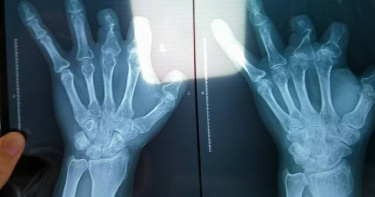

大傻眼!中國鄭州一名彭姓男子5年前因為意外不慎切傷左手,因此到醫院進行手術,過程中用了6個進口器材,總共花費10萬多元人民幣(約44萬新台幣),沒想到事後照X光卻發現,這些器材根本都不在他體內,讓他一氣之下告上法院。彭男向《新京報》透露,2017年11月他不小心切傷左手,到鄭州大學第一附屬醫院手術,檢查發現左手拇指、食指、中指、環指離斷傷,次日在全身麻醉下接受「指骨骨折切開復位內固定」,以及血管、神經、肌腱吻合術,收費顯示手術中使用6個微血管吻合裝置,共計100800元,但照X光時,卻顯示這6個「不可被分解、吸收」的進口器材,一個都不存在他體內。(圖/翻攝自新京報)據了解,9個對醫療器材有疑慮的患者,只有一人的手術紀錄載明「顯微鏡下利用血管吻合器裝置行血管吻合」,其他8人則未提及吻合血管使用了該器材。對此,主治醫師解釋,因手術中使用後發現血管未通暢,移除器材後手工吻合血管。不過,彭男反駁,如果不能吻合,為何連續使用6個才發現,認為情況不合理,因此已諮詢律師,考慮通過法律途徑解決問題。鄭州大學第一附屬醫院則回應,目前已對涉事的醫師停職調查,結果尚未出爐,若有最新進度會公開說明。消息曝光後,引發熱烈討論,「這樣的事可能不是第一次幹」、「這是發現的…」、「這不欺詐嗎?醫院還玩這個?」、「和詐騙有什麼區別,難道不觸犯刑法」。